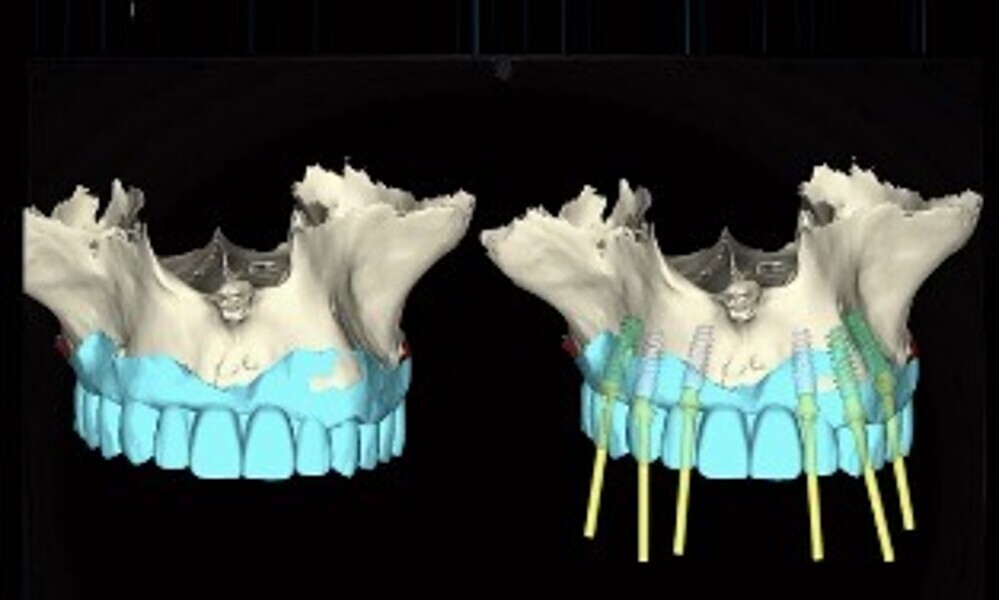

2. digital planning using coDiagnostiX (Dental Wings; 13–15);

3. surgical guide design in coDiagnostiX and 3D printing of the guide for the prosthetically driven drilling protocol (16 & 17);